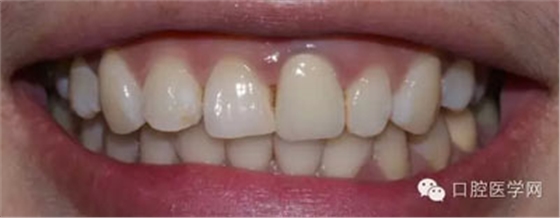

術(shù)前照

檢查:21金屬烤瓷冠修復(fù),顏色及形態(tài)與鄰牙不協(xié)調(diào),牙齦有輕微發(fā)黑,扣痛(-)、松動(dòng)度(-);11近中鄰面齲壞